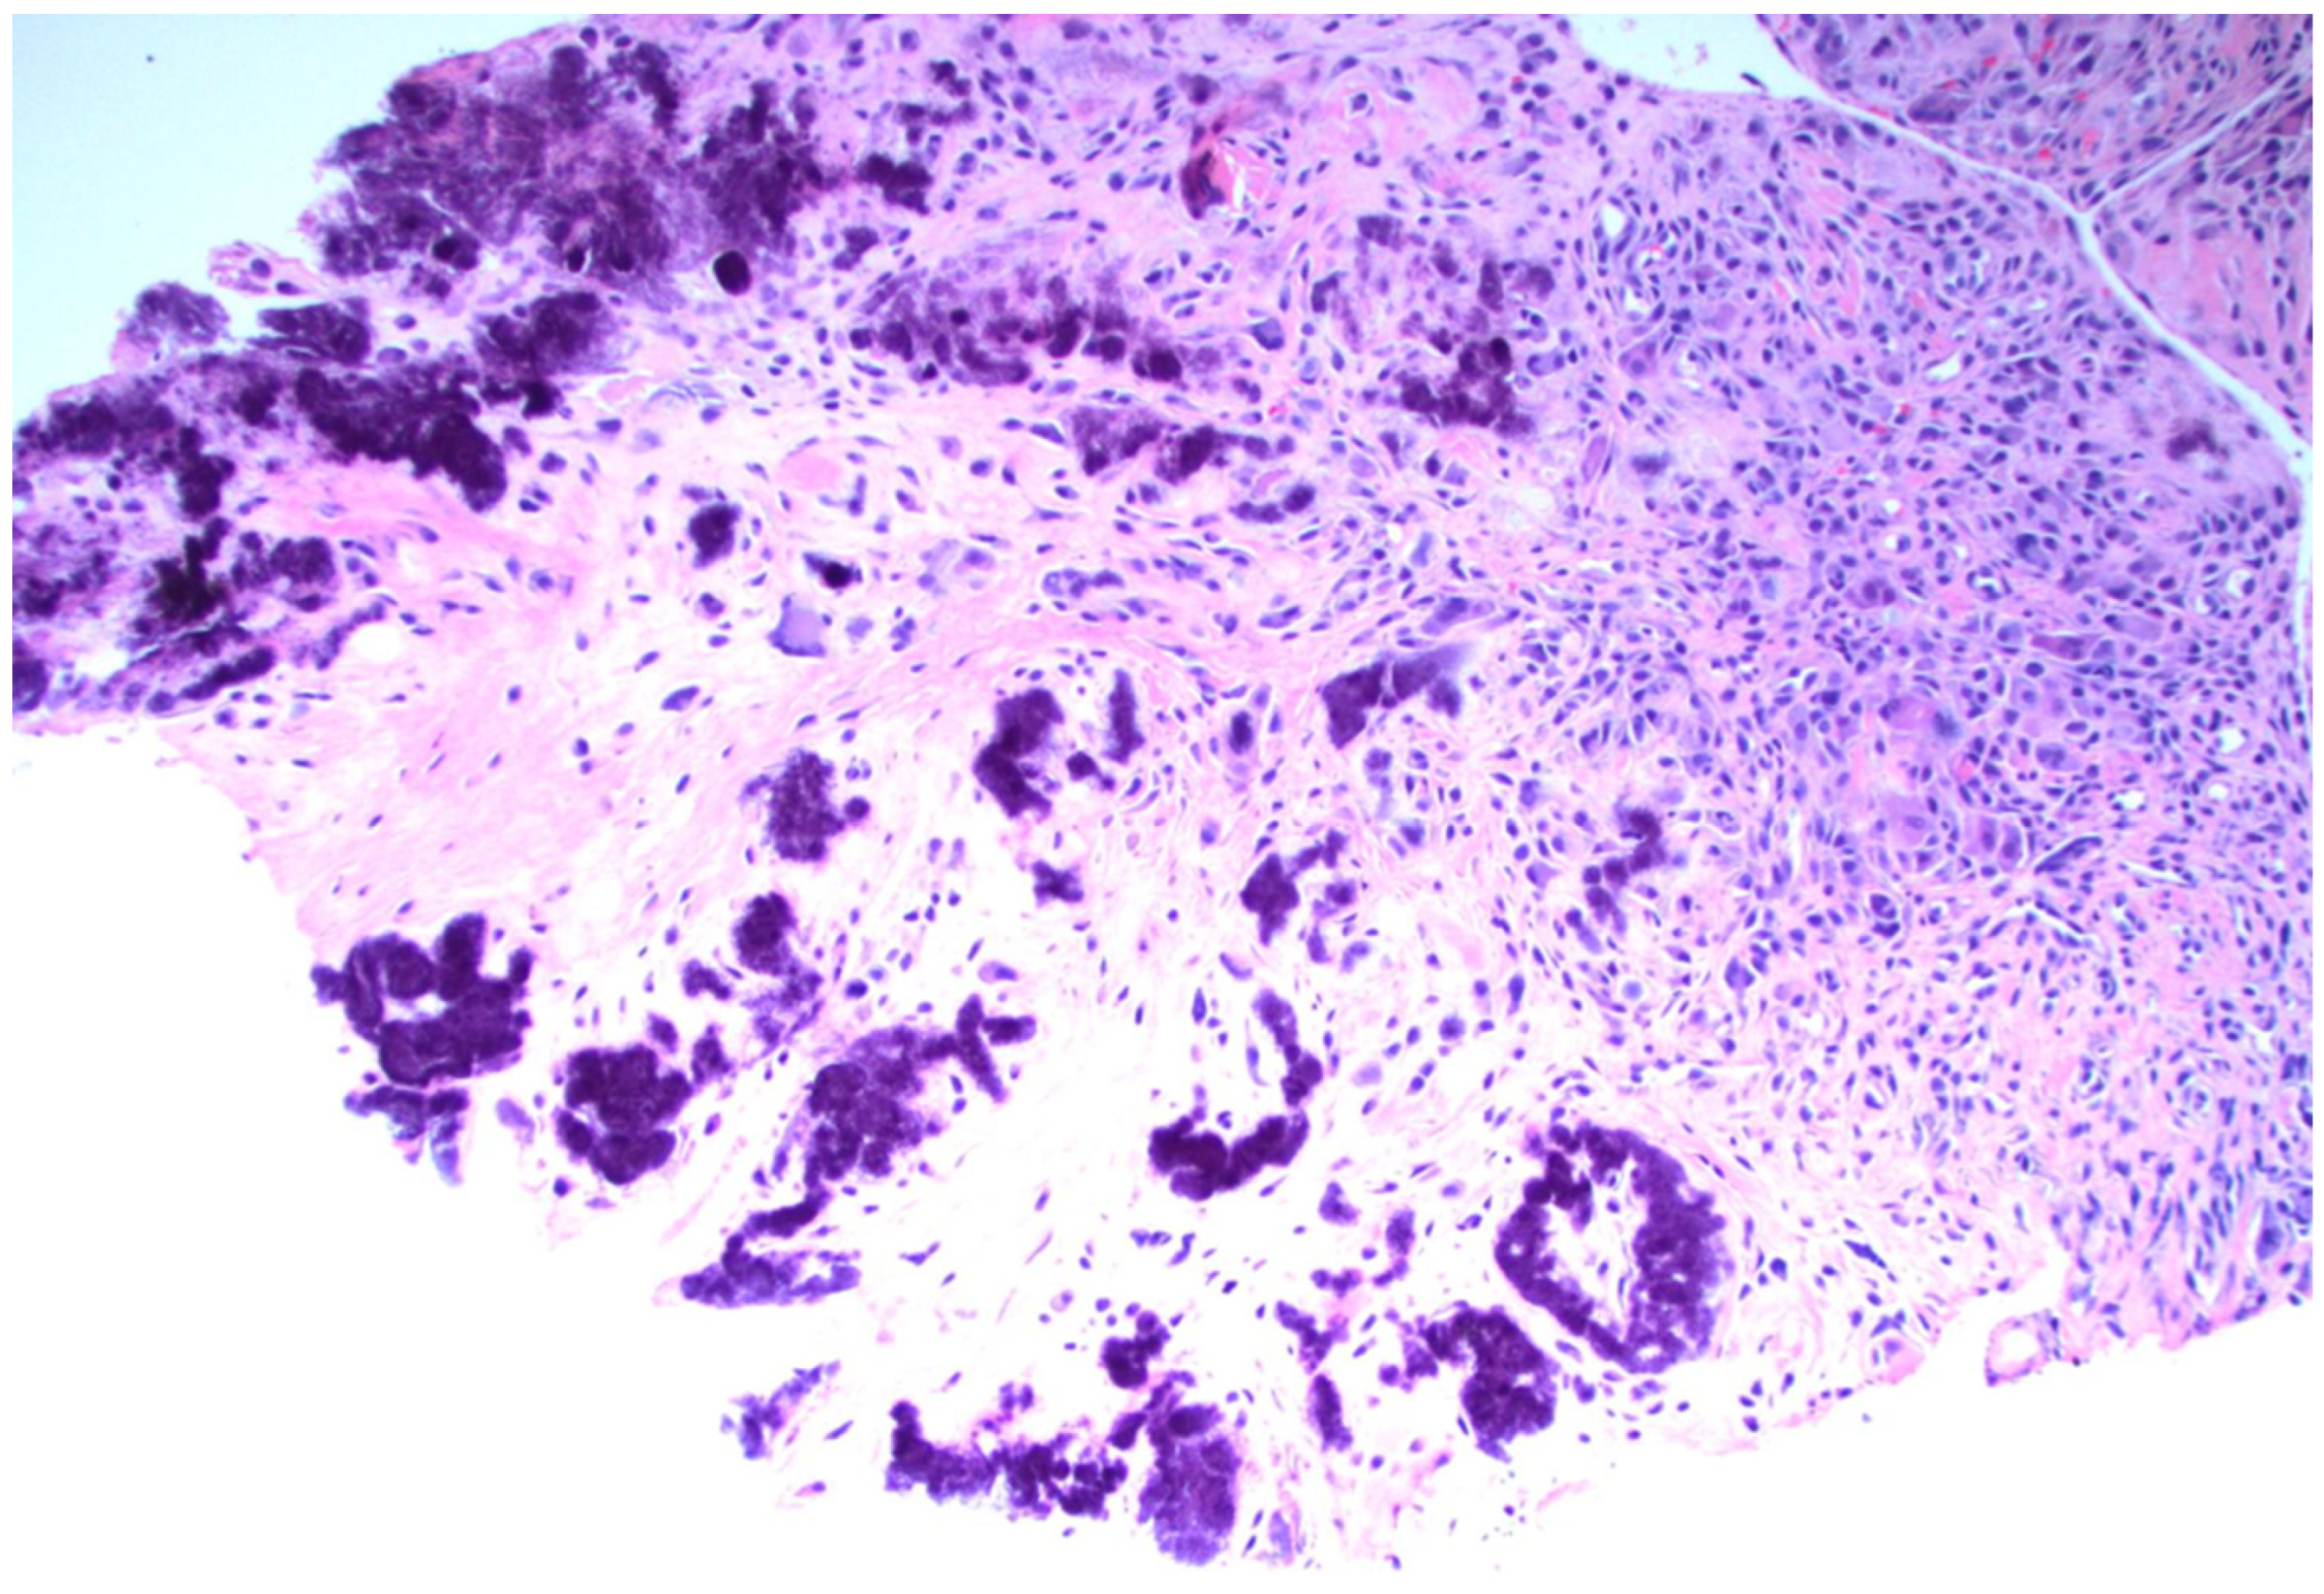

5.1. Disease-Specific Pathologic Findings—Gout

5.1.1. Crystals in Gout

5.1.2. Synovial Tissue Findings in Acute Gout

5.1.3. Synovial Tissue Findings in Chronic Gout

5.1.4. Tophaceous Deposits in Synovial Tissue